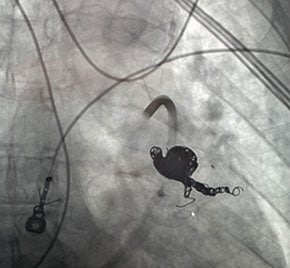

Hemoptysis treated with Embold Fibered​ Coils

Scan of vein before placement of coil. Visualizing the pulmonary artery​

Scan of vein after Embold fibered coil. After Embold Fibered placement​

Keshav Anand, MD

University of Utah

Salt Lake City, UT